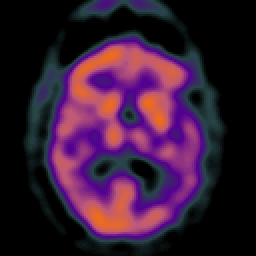

Subdural Hygroma,overlay -- Slice #26